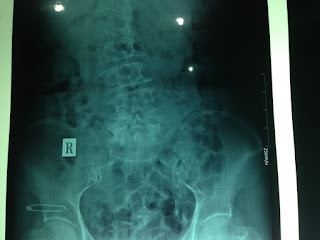

Thuốc lá có tác động trực tiếp hoặc gián tiếp gây giảm mật độ khoáng trong xương nếu không can thiệp sẽ gây loãng xương và hậu quả cuối cùng là gãy xương (gãy hay xẹp đốt sống, gãy cổ xương đùi, gãy đầu dưới xương cổ tay = gãy Pouteau colles…).Chất nicotine và các độc tố khác trong thuốc lá kích thích hình thành rất nhiều gốc tự do gây tổn hại đến từng tế bào trong cơ thể đặc biệt là huỷ các tạo cốt bào (osteoblast). TL gây giảm các nội tiết tố giúp xương chắc khoẻ (estrogen, testosterone) và tăng chất cortisol nên xương trở nên xốp, dễ gãy. Ngoài ra nicotine trong thuốc là còn gây tổn hại đến mạch máu nên các mô trong cơ thể trong đó có xương bị thiếu oxy và chất dinh dưỡng nên xương trở nên dòn, gãy tái phát và kéo dài thời gian liền xương.